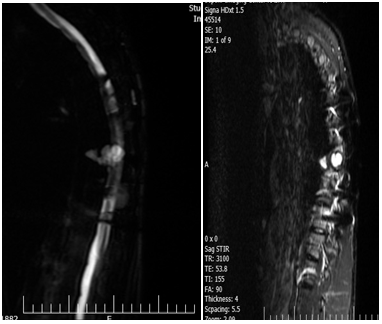

The magnetic resonance imaging (MRI) of thoracic spine revealed multiple well-defined extradural cystic lesions at T6-T8 level. There was cerebrospinal fluid (CSF) like signal intensities on T1- and T2- weighted images (Figures 3-5).

Figure 3: MRI showing extradural cystic lesions at T7-T8 level. There was cerebrospinal fluid (CSF) like signal intensities on T1- and T2- weighted images.